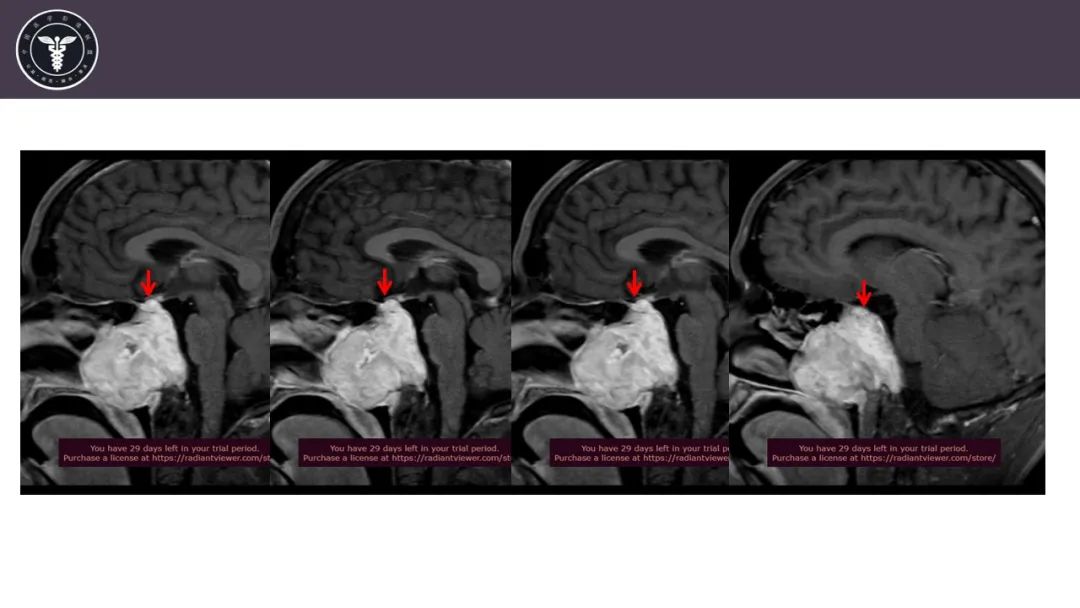

病例2

【病例】斜坡区骨巨细胞瘤 VS 脊索瘤-16